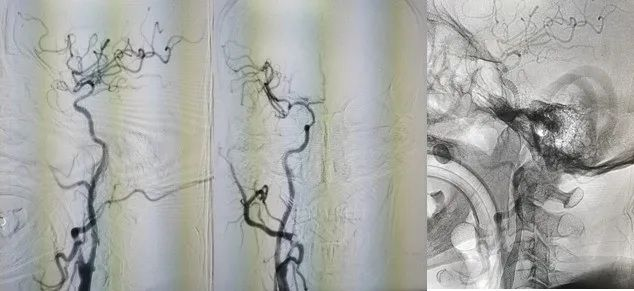

图2 造影见右侧颈内动脉起始处闭塞,闭塞处圆钝,可见自发再通后纤细扭曲血流,返流血较长,可达岩骨段-海绵窦段移行处

图3 通过前交通及后循环软膜支代偿,后交通未见明确开放,代偿情况可